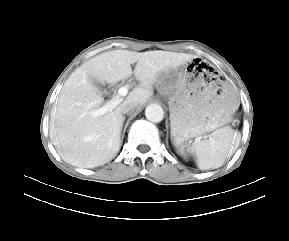

标题: CT19533:病变来源于哪?

患者,男,发现上腹部包块两月余。

病变位于肝胃间隙,实际就是位于小网膜囊(左肝下后间隙),呈轻度不均匀性强化,腹腔内及腹膜后见多发肿大淋巴结。所以我考虑肝胃间隙恶性胃肠间质瘤并淋巴结转移。

病灶强化不显著,灶周及腹膜后见多量淋巴结肿大,考虑淋巴瘤可能,其次考虑间质瘤

病灶与胰腺分界不清,来源于胰腺?

强化后病变与胃壁分界清楚,并且血供不是来源胃壁血管。考虑胰腺颈体癌并腹腔腹膜后淋巴结转移。